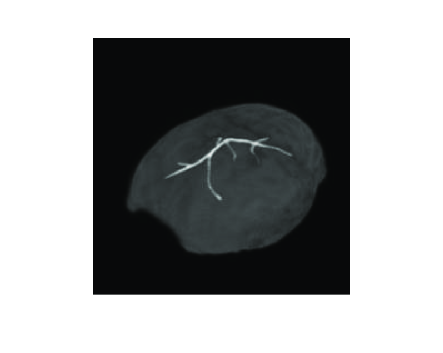

Figure 1: The (a) blood vessel and (b) disc numerical phantoms employed to represent 𝐩0subscript𝐩0\mathbf{p}_{0} in the 2D computer-simulation studies. Panel (c) is the overlapped image with 3D vessel phantom and skull, which is only used to show the relative position of the phantom to the skull.

Numerical phantoms: The two numerical phantoms shown in Fig. 1-(a) and (b) were chosen to represent the initial pressure distributions 𝐩0subscript𝐩0\mathbf{p}_{0} in the 2D computer-simulation studies. The blood vessel phantom shown in Fig. 1-(a) was employed to investigate the robustness of the reconstruction methods with respect to different types and degrees of data incompleteness mentioned above. The low contrast disc phantom displayed in Fig. 1-(b) was employed to investigate the robustness of the reconstruction methods with respect to errors in the SOS and density maps introduced below.

Because PACT is inherently a 3D method, we also conducted 3D simulation studies to evaluate and compare the iterative reconstruction method and the TR method. As in the 2D studies described above, the 3D SOS and density maps were representative of a monkey skull. A 3D blood vessel phantom was positioned underneath the skull to mimic the blood vessels on the cortex surface. To demonstrate this configuration, Figure 1-(c) shows the overlapped images of the 3D phantom and the skull. The assumed scanning geometry was a hemispherical cap with radius of 46 mm, and 484 transducers were evenly distributed on the hemispherical cap by use of the golden section spiral method [46]. The pressure data were computed on a 512×512×256512512256512\times 512\times 256 grid with a pitch of 0.2 mm and a time step Δt=30Δ𝑡30\Delta t=30 ns. The simulated pressure data were then contaminated with 3% AWGN. The TR reconstruction method employed 2,000 temporal samples at each transducer location, whereas the iterative method employed 1,000 samples.